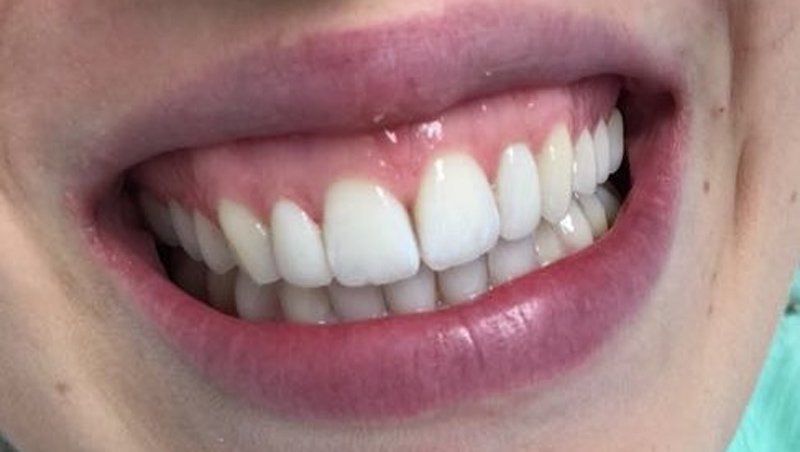

Sbiancamento con led

Button